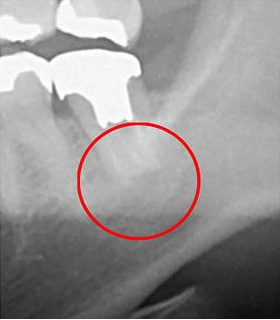

下はCTとレントゲンで撮影したものを比較した画像です。

赤い丸で囲ったのが問題のある部分ですが、レントゲン写真では問題のある部分が写し出せていません。

問題のある場所が分からなければ、適切な治療はできません。どこに問題があるかを正しく把握することが根管治療では大切になってきます。